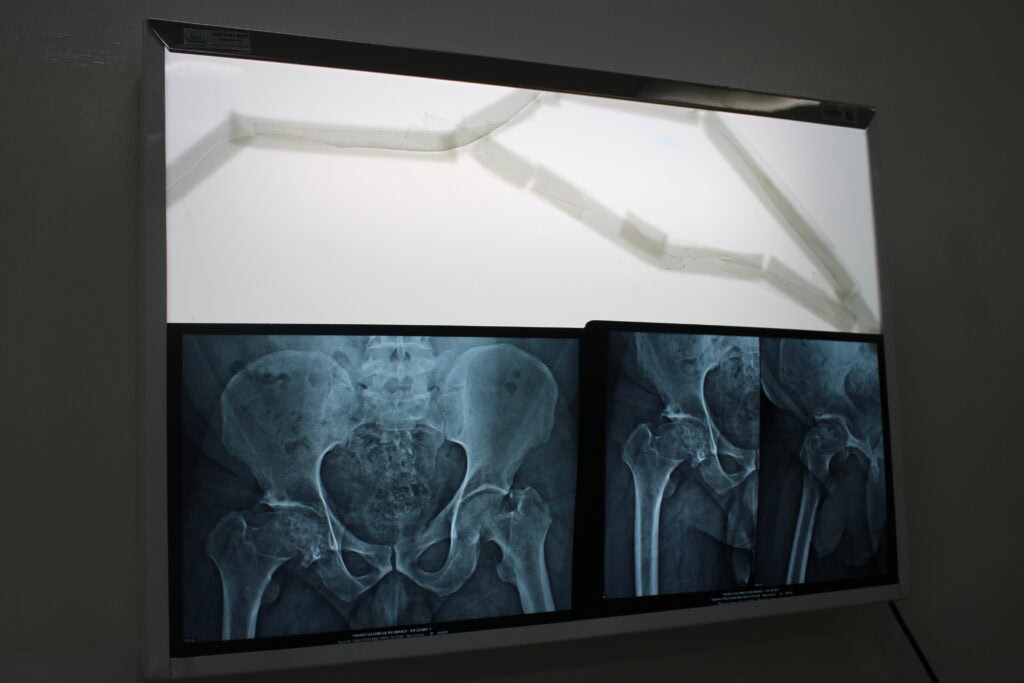

O médico ortopedista Demian Miziara, que conduziu a cirurgia ao lado do também especialista Gleykn Trzeciak, explicou a razão pela qual a prótese de cerâmica se destaca em pacientes jovens, a exemplo de Edgleyson.

“Essa prótese é usada principalmente em pacientes jovens. É uma cirurgia que traz uma melhora da qualidade de vida realmente impressionante. Quando você coloca, é para o resto da vida do paciente e quando o paciente é jovem, abaixo de 60 anos, ele é mais ativo, tem mais tempo de longevidade, então a prótese precisa ser de materiais mais resistentes. É nessas situações que usamos a cerâmica. Tem outros tipos de materiais, como o polietileno com metal, mais indicado para quem tem acima de 60 anos, que é o padrão”, esclareceu o cirurgião.

O ortopedista complementou que realizar um procedimento como este no Sistema Único de Saúde no Acre representa um grande passo. “Representa muito conseguir utilizar esse tipo de material de alta complexidade e não está na tabela para fornecimento em livre demanda, por isso, é preciso cumprir um processo jurídico e administrativo até a liberação. Os pacientes que passam por essa cirurgia normalmente têm um resultado excepcional. Recuperam a qualidade de vida. Hoje mesmo o Edgleyson já vai poder se sentar; amanhã ele começa a dar os primeiros passos, sempre com muito cuidado, porque os primeiros seis meses são delicados, mas com fisioterapia ele fortalece, estabiliza e depois leva praticamente uma vida normal”, ressaltou.